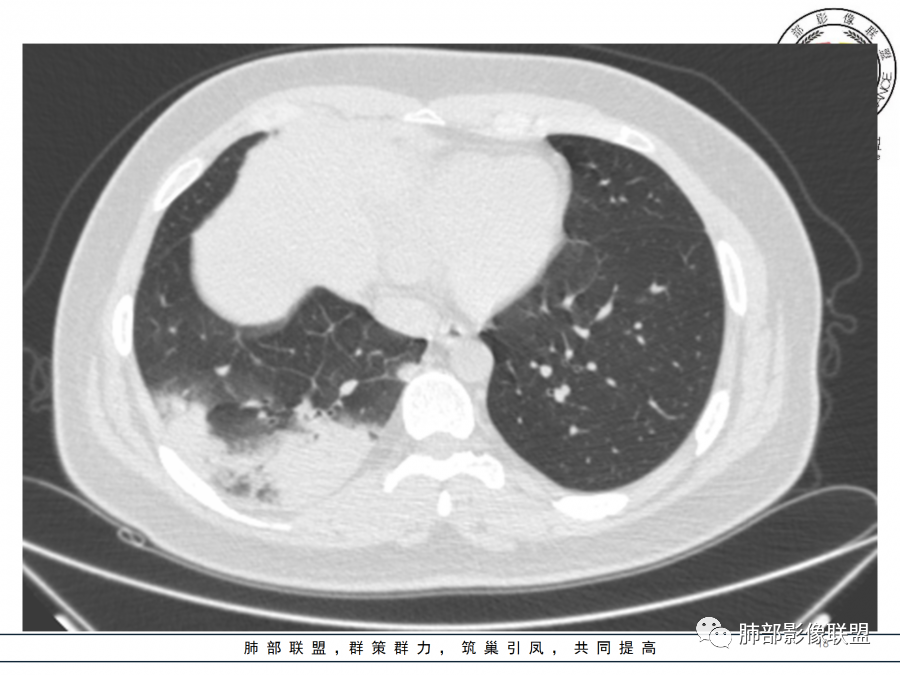

大叶性肺炎是外周向中心的,与胸膜垂直的,沿着气道方向,隐球菌是平行胸膜的,我感觉是肺小叶内的肺泡起源

南边

隐球菌沿胸膜下分布,不受段的局限,沿肺实质朝周围蔓延

这个病变也不是一个起源中心,胸膜下,多发结节状、实变影。而大叶性肺炎多数由内-外大片状。所以是肺实质多发融合病变。单纯从影像上,还是比较符合隐球菌特点,胸膜下,多发、多中心,相互融合(兄弟齐心)。

隐球菌,胸膜下病灶,多个起源中心,最终还是融合在一起,侧向融合为主的。

隐球菌,侧向融合、外围胸膜下为主,也有累及叶段的、比较少。

隐球菌之顺口溜(影像征像版)在那遥远的边远山区——胸膜下生活着一群蘑菇兄弟——性质相同多结节表面虽脏,内心实诚——有晕,一般无空洞扮扮鬼脸,偶尔调皮——鬼脸征撞墙就跑,颇有灵性——一般不引起胸膜增厚积液气管通畅或进门才堵,只为空气——不会堵门口周围蔓延,不乱播散,死心踏地——不走淋巴,气管,血道播散。污头垢面,家里干净,只因免疫不低,神采奕奕——空洞干净,注意:以上不适用于免疫力低下病人。

1)实变影为大小不等多中心性。

2)沿胸膜下分布趋势(不同于大叶性肺炎的肺叶“造型”)。

3)周围较大范围磨玻璃影及小叶间隔增厚。

4)病灶体积增大明显(叶间裂推移)。